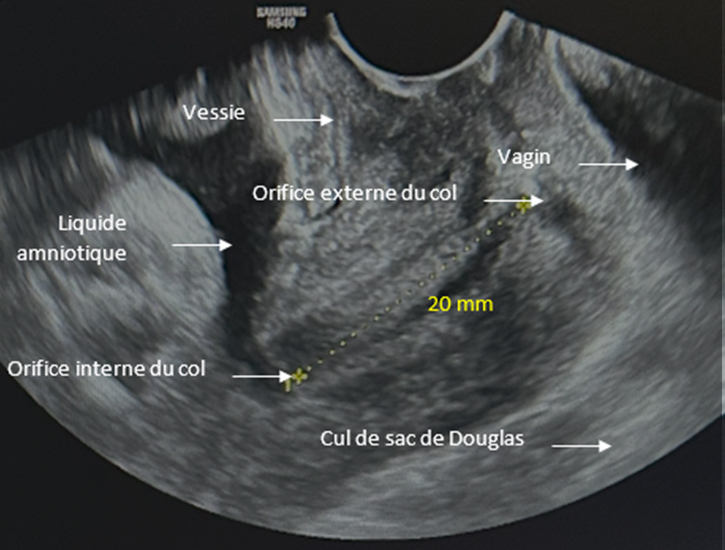

Voici le résultat de la cardiotocométrie et de l’échographie du col réalisée par voie endovaginale.

Figure 4 (Rodolphe Matias de Sousa, La Revue du Praticien)

Figure 5 (Rodolphe Matias de Sousa, La Revue du Praticien)

Une menace d’accouchement prématuré se définit comme des contractions utérines régulières et douloureuses (ici 5 par dix minutes visibles à la tocométrie) et un col raccourci ou modifié cliniquement (ici mesuré à 20 mm à l’échographie endovaginale). Un col non modifié est dit long, tonique, postérieur, fermé avec une présentation fœtale non sollicitante.

Concernant l’échographie endovaginale.

Figure 7 (Rodolphe Matias de Sousa, La Revue du Praticien)